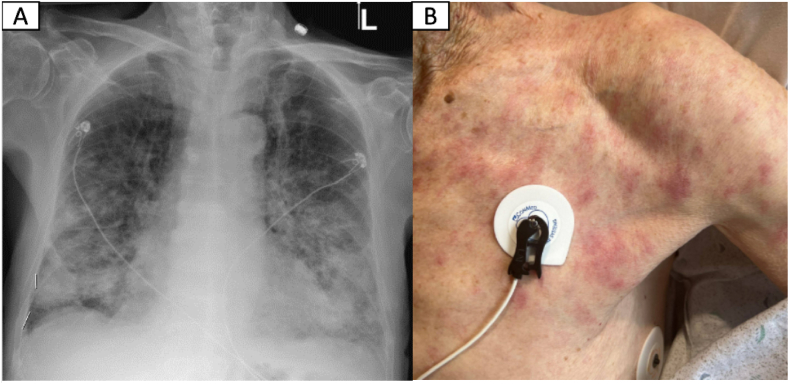

An 89-year-old male with a medical history of non-ischemic cardiomyopathy was initially admitted with acute hypoxic respiratory failure attributed to heart failure exacerbation. Aside from progressive dyspnea, a non-pruritic, non-painful rash and constitutional symptoms were reported. Initial work-up was remarkable for normocytic anemia, lymphopenia, mild hypercalcemia, and elevated inflammatory markers. Despite aggressive diuresis, his respiratory distress worsened requiring up-titration of supplemental oxygen (6–8L/min). Subsequent chest CT showed diffuse, ill-defined areas of consolidation and ground-glass opacities (GGOs) with areas of solid and ground-glass nodularity. Rheumatologic work-up was remarkable for mildly elevated ANA titer of 1:60, and positive anti-centromere antibody of 1.8 AI (normal range 0–0.9 AI). Infectious work-up was negative. Due to high oxygen requirements, tissue sampling was obtained by skin biopsy instead of bronchoscopy. After biopsy testing, prednisone 60 mg was started with posterior clinical and radiographic improvement. Biopsy results revealed cutaneous MZL. Follow-up PET scan showed persistent but improved diffuse GGOs and nodular opacities. Given the clinical presentation, imaging and skin biopsy results, the diagnosis was compatible with EMZL with synchronous pulmonary and skin manifestations. Empiric treatment with Rituximab and steroid taper was planned. At 6-month follow-up, the patient reported clinical and respiratory improvement.